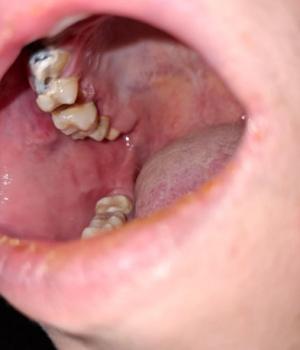

What Is Seen in This Case

The image shows a localized red area on the gum near the side teeth, highlighted in the photo. The teeth themselves appear mostly intact, but the gum tissue in this area looks inflamed and irritated. This type of lesion is often related to local trauma, irritation, or early infection.